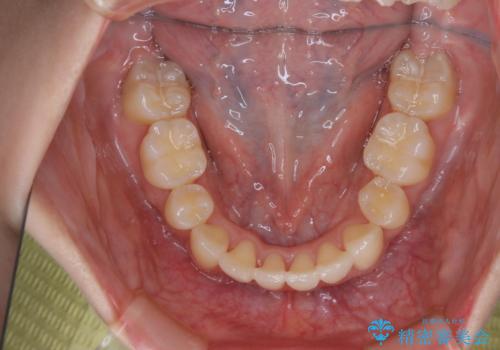

開窓して器具で力をかけても動く様子がなかったため抜歯とし、小臼歯を犬歯に見立てて治療を完了しました。

結果的に見た目の違和感もなく、期間の短縮にもつながりました。

- 治療期間

- 1年6ヶ月